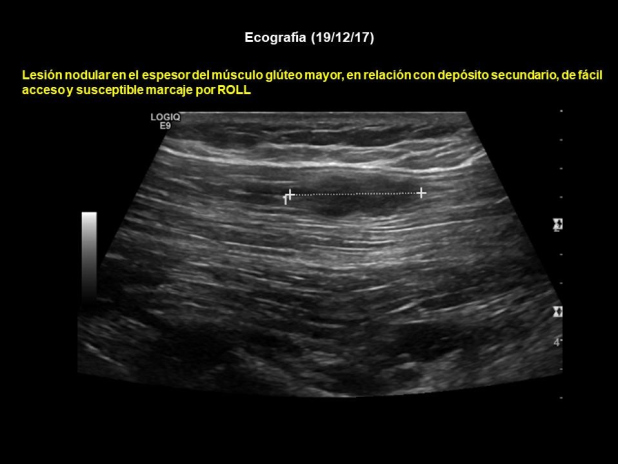

Se realiza PET-CT (7/12/17) previo a resección de adenopatía inguinal izquierda (Figs. 3 y 4), hallándose lesión focal de 14 mm con incremento de actividad metabólica (SUV 8,3) situada a nivel del músculo glúteo mayor izquierdo sugestivo de implante secundario, sin traducción morfológica en CT. Además, adenopatía inguinal izquierda con incremento de la actividad metabólica (17mm/SUV 4) compatible con posibles cambios inflamatorios secundarios a punción reciente. Una nueva ecografía muestra lesión nodular en el espesor del músculo glúteo mayor, en relación con depósito secundario, de fácil acceso y susceptible de marcaje por ROLL (Fig. 5). También se encuentran dos adenopatías inguinales izquierdas, con criterios de posible secundarismo ganglionar.